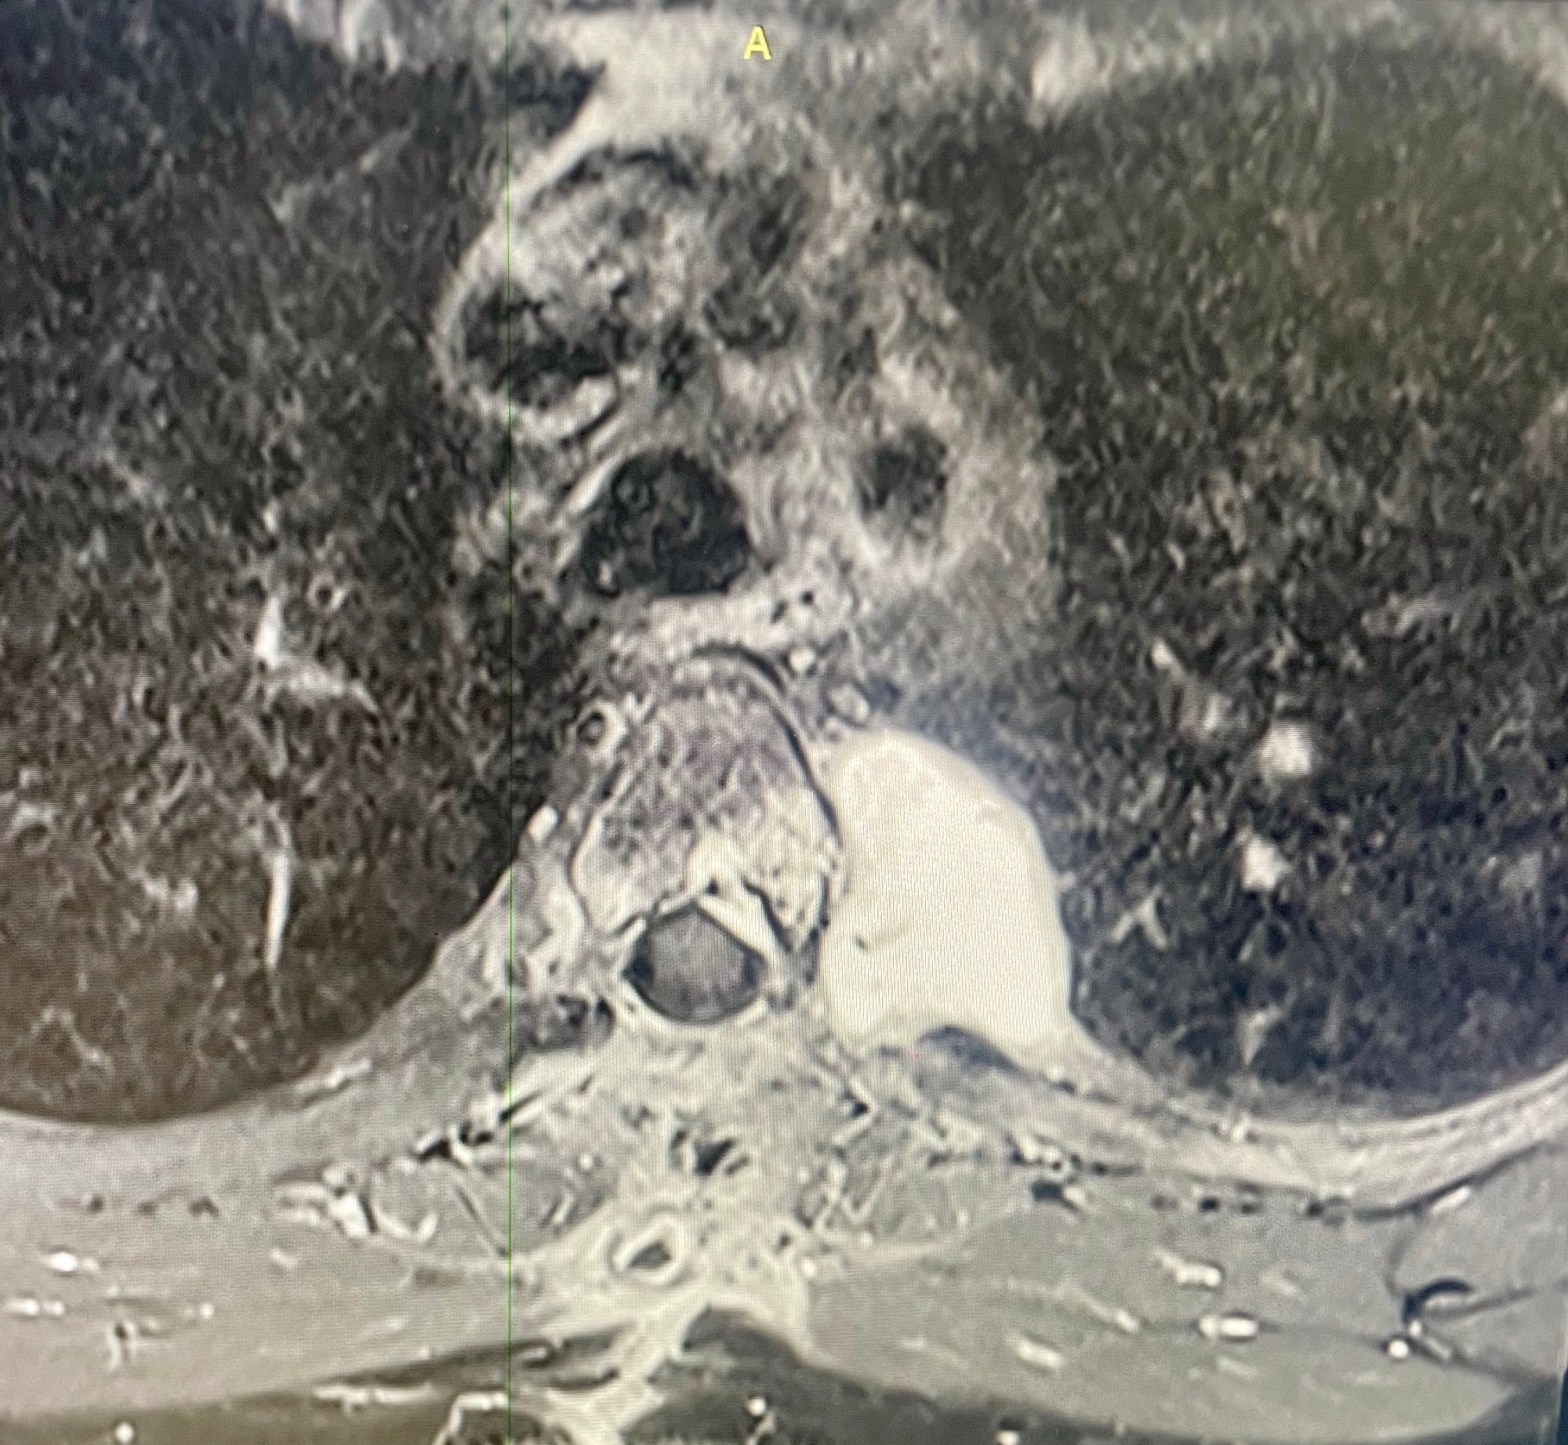

I neurinomi (o schwannomi) toracici a clessidra sono tumori benigni a lenta crescita che originano dalla guaina dei nervi spinali. La loro caratteristica “a clessidra” deriva dalla particolare forma che assumono, estendendosi a cavaliere del forame di coniugazione (il passaggio tra il canale spinale e la gabbia toracica), posizionandosi in parte dentro il canale spinale e in parte nel mediastino posteriore. Il trattamento è combinato e consiste nella asportazione della porzione intra spinale da parte del neurochirurgo e di quella intratoracica da parte del chirurgo toracico.

Nel caso in esame si è proceduto all’asportazione del neurinoma intratoracico con tecnica robotica dopo il trattamento neurochirurgico. Il tubo di drenaggio è stato rimosso 24 ore dopo l’intervento ed il paziente dimesso in seconda giornata